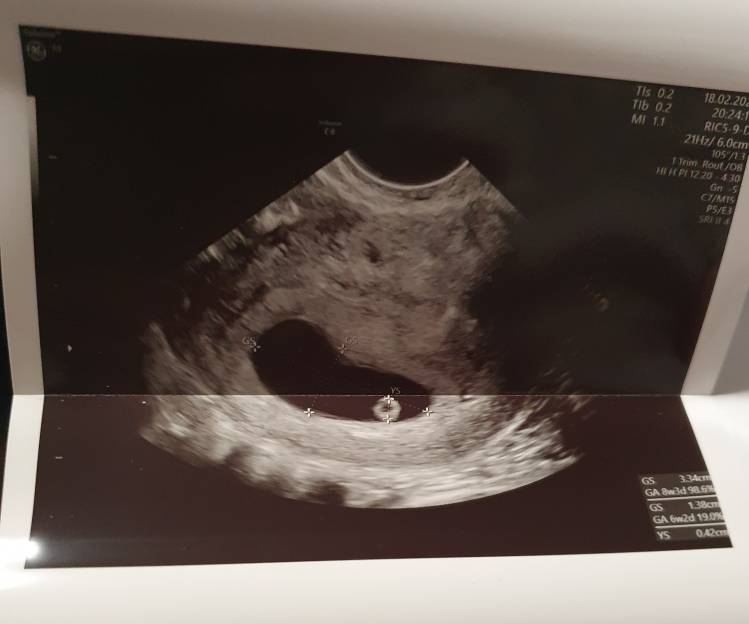

My też już po wizycie ❤ co prawda serduszko jeszcze nie bije- ciąża o wiele młodsza niż wychodziłoby z terminu ostatniej @- ale tego się spodziewałam, bo cykle nieregularne, następna wizyta w przyszły czwartek, liczymy że usłyszymy ❤, dzidzia ma prawie 3 mm- przełom 5/6 tygodnia. Dostałam progesteron, zwiększamy dawkę Euthyroxu- jutro idę na badania plus krzepliwość bo wcześniej miałam z nią problemy.

My też już po wizycie [emoji173] co prawda serduszko jeszcze nie bije- ciąża o wiele młodsza niż wychodziłoby z terminu ostatniej @- ale tego się spodziewałam, bo cykle nieregularne, następna wizyta w przyszły czwartek, liczymy że usłyszymy [emoji173], dzidzia ma prawie 3 mm- przełom 5/6 tygodnia. Dostałam progesteron, zwiększamy dawkę Euthyroxu- jutro idę na badania plus krzepliwość bo wcześniej miałam z nią problemy.